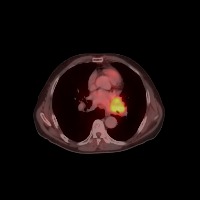

Diagnostic Aid in Medical Imaging: Radiologists could use this model to identify and characterize lymph node tumors in CT scans, assisting in early detection and diagnosis of potential cancerous growths.

Medical Research: Researchers might employ the model to study the characteristics and progressions of various types of lymph node tumors, towards producing more effective treatments and prevention strategies.

Training Medical Students: This model could serve as an invaluable tool for training medical students or residents in radiology, allowing them to familiarize themselves with the appearance and location of different lymph nodes, as well as to recognize varied tumor classifications.

Telemedicine: In remote or rural areas lacking immediate access to expert radiologists, this model can come handy as it assists primary care providers or mid-level practitioners in identifying lymph node tumors and making more effective referrals.

Second Opinion: Patients with possible lymph node tumors might use the model as a 'second opinion' to verify diagnoses, ensuring there are no oversights in their scans.